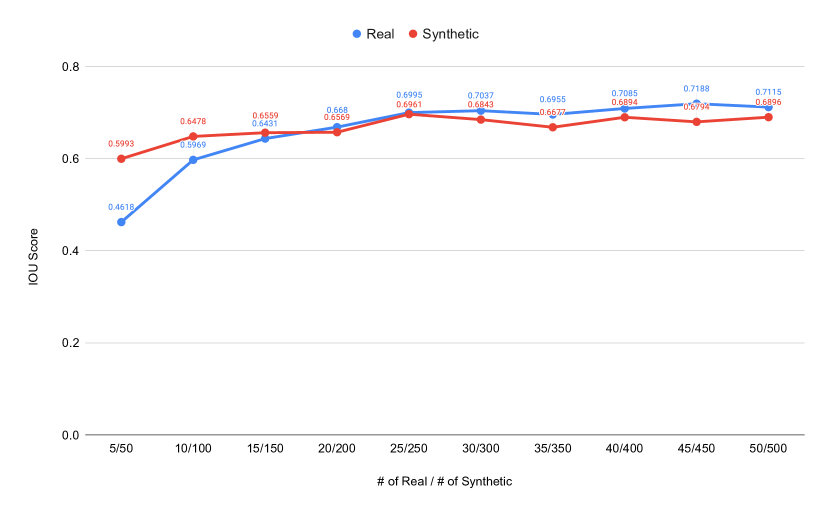

The main purpose of these experiments is to find the effect of using synthetic data generated from the SinGAN-Seg pipeline instead of small real datasets because the SinGAN-Seg pipeline can generate an unlimited number of synthetic samples per real image. A synthetic sample consists of a synthetic image and the corresponding ground truth mask. Therefore, experts’ knowledge is not required to annotate the ground truth mask. For these experiments, we have selected the best parameters of the SinGAN-Seg pipeline from the experiments performed under Section Synthetic data versus real data for segmentation. First, we created small sub-datasets from the real polyp images from fold one such that each dataset contains number of images, where can be one of the values of . The corresponding synthetic dataset was created by generating synthetic images and corresponding masks per real image. Then, our synthetic datasets consist of number of images such that . Then, we have compared true pixel percentages of real masks and synthetic masks generated from the SinGAN-Seg pipeline using histograms of bin size of . The histograms are depicted in Fig 10. The first row represents the histograms of real small detests, and the second row represents the histograms of corresponding synthetic datasets. Compare pairs (one from the top row and the corresponding one from the bottom) to get a clear idea of how the generated synthetic data improved the distribution of masks.

The UNet++ segmentation models were trained using these real and synthetic datasets separately. The synthetic dataset is generated using style transfer ratio because it shows the best performance in the experiment, which uses only fake data to train segmentation models as presented in Table 2 in addition to the best SIFID values presented in Table 1. Then, we have compared the performance differences using validation folds. In these experiments, the training datasets were prepared using fold one. The remaining two folds were used as validation datasets. The collected results from the UNet++ models trained with the real datasets and the synthetic datasets are tabulated in Table 3. A comparison of the corresponding IOU scores are plotted in Fig 11.

In this experiment, we have evaluated how synthetic data can be used instead of small real datasets, such as images per dataset. Results collected from these experiments show that synthetic segmentation datasets can produce better segmentation performance when the corresponding real datasets are small. For the smallest dataset, the performance gain is around in term of IOU score.

This study showed that the synthetic data generated from a small real dataset can improve the performance of ML models for image segmentation. For example, when the real polyp dataset size is to train our UNnet++ model, the synthetic dataset with samples showed improvement over the IOU score. Similarly, when the real dataset is and the corresponding generated dataset is (we always take times as the real dataset in our case studies, but there is no any limit.), the synthetic dataset shows an improvement over the real dataset. These experiments emphasize that SinGAN-Seg generated synthetic data can be used instead of small real datasets.